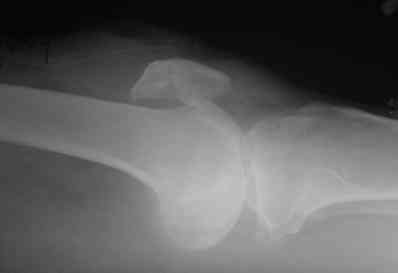

В приложении фото пациента с переломом надколенника 3 месячной давности.

После мобилизации отломков,  4 главой мышцы бедра и полного разгибания

голени оставался диастаз между костными фрагментами в 2 см. В связи с

этим наложили  модуль из аппарата Илизарова  - 2 опоры и 2 спицы (в

верхнем полюсе надколенника и верхней трети большеберцовой кости). Очень

медленно (в течение 15 минут) путем накручивания гаек на стержнях

растянули 4 главую мышцу бедра и устранили диастаз. Аппарат

демонтировали и выполнили остеосинтез ?стягивающей петлей?. Через 6

месяцев фиксаторы удалены. Автор данного ?хирургического трюка?

профессор из Австрии Vilmos Vecsei (?Гений ортопедии?, 2004, No 4, С.

94-95). Ваш случай не совсем идентичный по давности травмы и малой

величине дистального отломка, но описанный ?трюк? может оказаться

полезным и при выполнении операции, которую рекомендует Джолдас.